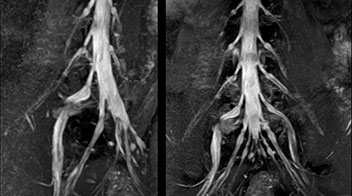

“In such case, we would then browse through axial T2-weighted MR images slice by slice and mentally reconstruct the actual situation based on both radiculography and MRI. Fortunately, NerveVIEW can now very well show nerve courses and presence of nerve compression or edema in one single image series.” “We have often seen NerveVIEW directly depict details of the nerve compression that were not observed by radiculography. Therefore, we think that with NerveVIEW we can reduce the number of invasive examinations, especially for some patients with lumbar plexus symptoms.”

“Before NerveVIEW, diagnosis by MRI alone was sometimes difficult, unless there was a strong suspicion based on clinical symptoms,” says Shoji Yabuki, MD, DMSc, Orthopedic surgeon at Fukushima Medical University School of Medicine. “This is why we routinely perform selective lumbosacral radiculography (nerve root block) and x-ray in such cases. However, radiculography can only depict nerves as far as the contrast agent reaches. When a nerve is distorted by compression, the contrast agent will not pass through this compressed area, preventing us from evaluating the full nerve compression.”

The key concept in MR neurography, Dr. Yabuki stresses, is the ability to directly visualize spinal nerves, versus inferring the presence of pathology indirectly. “Before NerveVIEW, we estimated compression of the nerve by looking for the presence or absence of fat signal on other MR images,” he says.

“NerveVIEW can clearly show nerve courses and presence of nerve compression. However, when multiple abnormalities are seen, it can still be hard to determine which nerve is causing the symptoms,” says Dr. Yabuki. “In our experience so far, we see abnormal findings on NerveVIEW in about 70% of elderly patients. As the pain is usually caused by only one nerve, we thus need to find the exact corresponding nerve.” “With a nerve root block, the patient's pain is improved by infiltration of local anesthesia directly around the nerve root considered to be responsible. Knowing such nerve root block findings prior to image interpretation, helps to easily recognize abnormal findings on NerveVIEW as well. In other words, without a priori knowledge, based on symptoms and/or nerve root block findings, we must be aware of the possibility of overdiagnosis.”